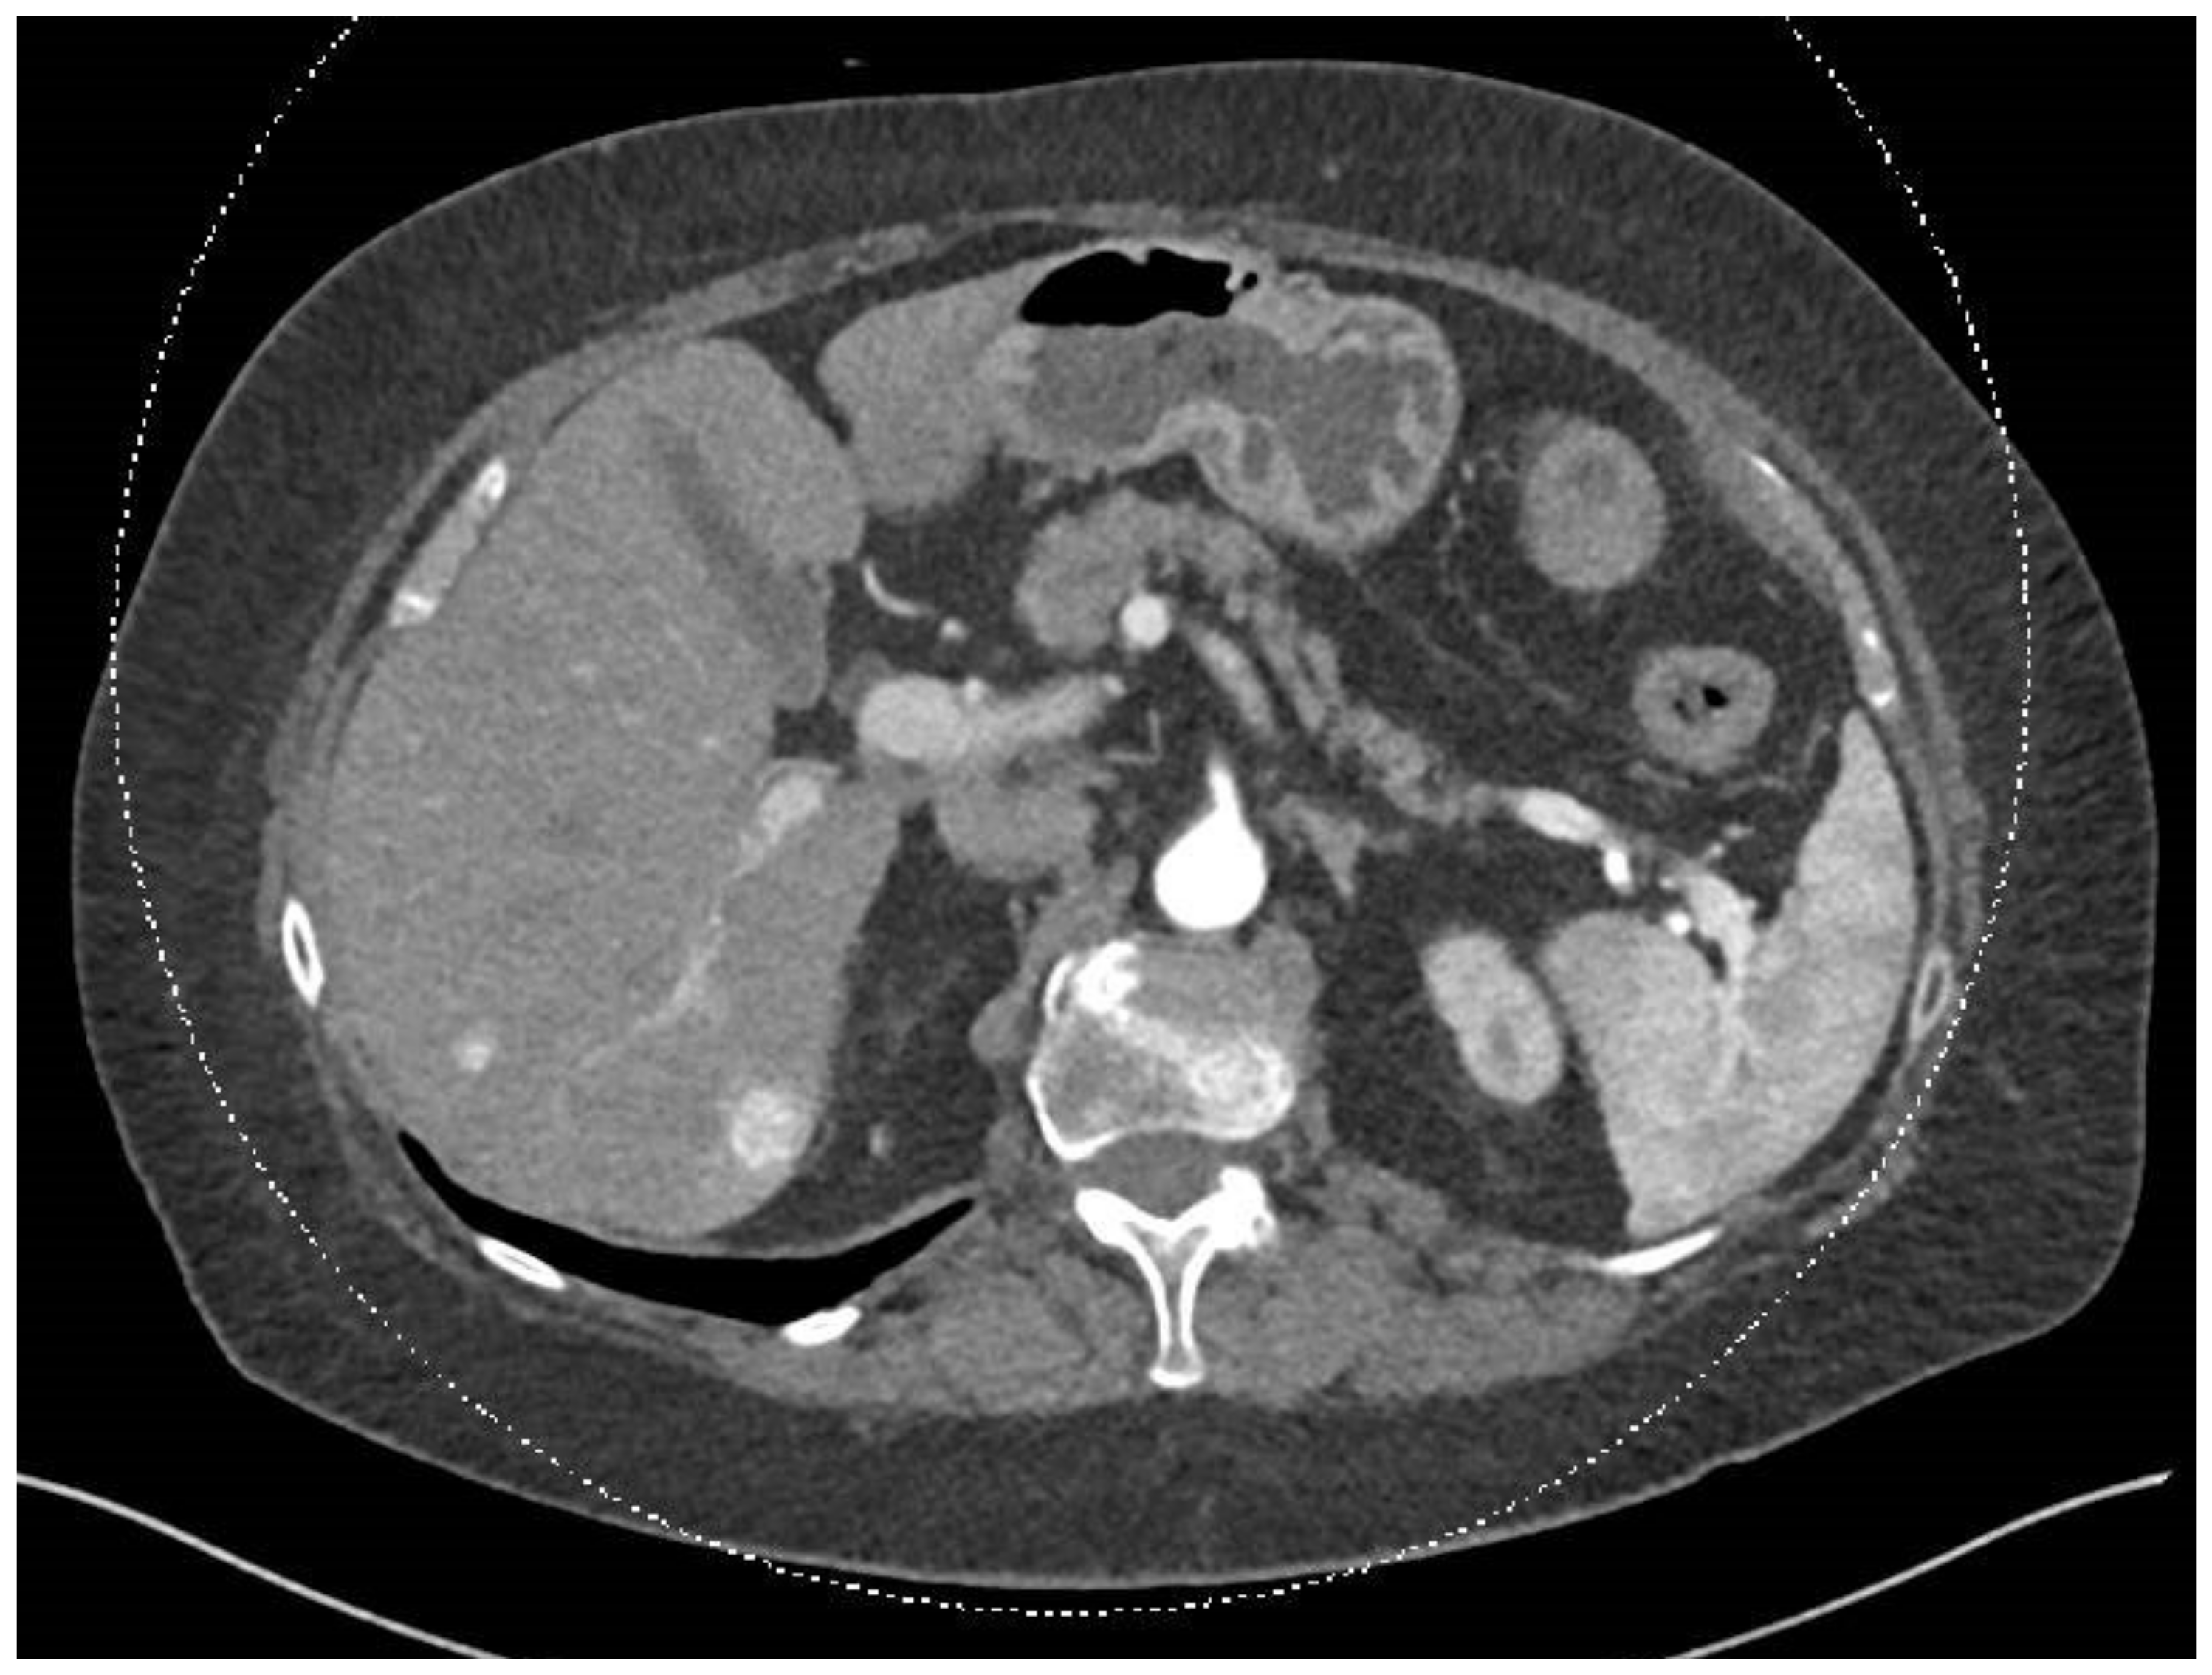

In December 2023, a full-body CT scan revealed that two known liver metastases had grown, and a new lesion had appeared near the inferior vena cava (IVC) in the liver. A multi-phase liver CT protocol performed later in December identified five lesions in the right liver lobe and at least one lesion in the left lobe (Figure 1). After consultation with an interventional radiologist, it was determined that the disease spread pattern was unsuitable for chemoembolization. Still, it was appropriate for selective internal radiation therapy (SIRT) using Yttrium-90. In February 2024, approximately one week before SIRT treatment, the patient underwent preparatory hepatic catheterization and selective simulation using Tc-99mma, demonstrating the feeding arteries to the liver tumors, and a low lung shunt fraction of 9% was calculated. During this preparatory hepatic catheterization simulation, the arteries feeding the tumors were mapped, allowing optimal catheter location placement (Figure 2). On 8 February 2024, the SIRT procedure was conducted under general anesthesia due to the patient’s back pain and inability to lie flat; a puncture was performed under local anesthesia, with fluoroscopy and ultrasound guidance, in the right common femoral artery. Catheterization of the superior mesenteric artery (SMA) was performed, and pressure injection showed no vessels from the SMA supplying the tumor. Subsequently, catheterization of the celiac artery was performed, with automatic injection showing celiac artery anatomy and pathological tumor enhancement in both liver lobes, particularly in the right lobe. A branch from the common hepatic artery was identified, supplying part of the right liver lobe, including at least two tumors. An accessory branch to the left lobe was observed through the left gastric artery, though it did not supply the liver tumors. Three doses of technetium were injected selectively into the right hepatic artery distal to the cystic artery, the left hepatic artery and a branch supplying part of the tumors in the right lobe, which originates from the proximal common hepatic artery. Due to the proximity of the origin of the right gastric artery, embolization with 2 mm coils was performed. At the end of the scan, the patient was transferred to the Nuclear Medicine Department, which showed a minimal lung shunt (9%) with no evidence of gastrointestinal shunt. The patient was then returned to the angiography suite for the second phase of the procedure. Selective catheterization of the three arteries was repeated, and technetium was injected with a total calculated dose of 1.4 GBq (0.4 to the left lobe, 0.4 to the systolic artery in the right lobe, and 0.5 to the right hepatic artery distal to the cystic artery). SIRT treatment was performed successfully with no apparent complications, and the patient was discharged home the next day.

Figure 1.

This abdominal and pelvic CT with contrast, performed on 25 December 2023, was compared to the previous abdominal CT from 15 August 2023 and the chest CT from 9 December 2021. The liver demonstrated two hypervascular lesions consistent with SFT: one lesion in segment 8 measuring 0.9 cm, previously 0.6 cm, and another lesion in segment 6 measuring 1.5 cm, previously 1.3 cm.